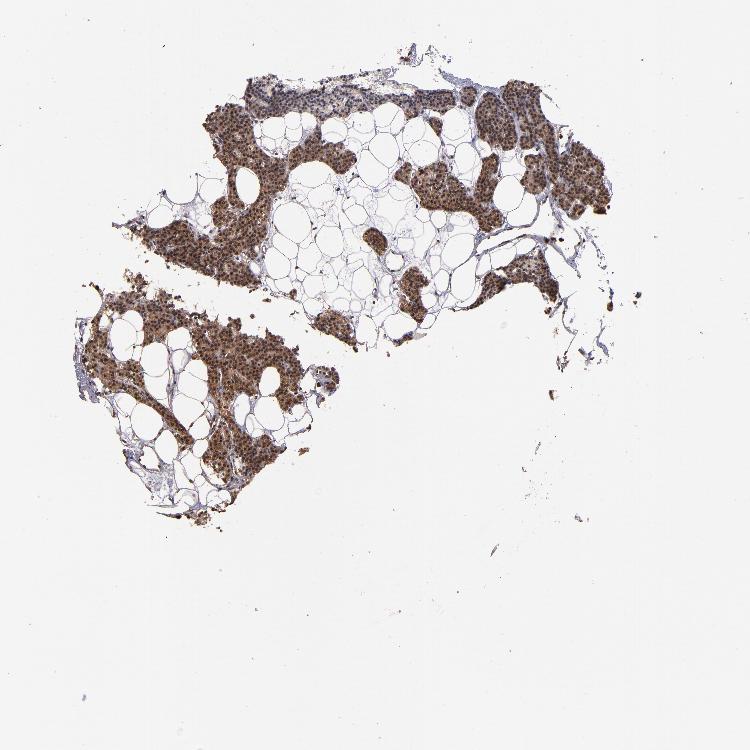

PARATHYROID GLAND - Antibody stainingi

Antibody staining in the annotated cell types in the current human tissue is reported as not detected, low, medium, or high, based on conventional immunohistochemistry profiling in selected tissues. This score is based on the combination of the staining intensity and fraction of stained cells.

Each image is clickable and will lead to virtual microscopy that enables deeper exploration of all samples and also displays staining intensity scores, fraction scores and subcellular localization as well as patient and tissue information for each sample.

Antibody HPA003054Antibody CAB046029

Glandular cells MediumNot detected